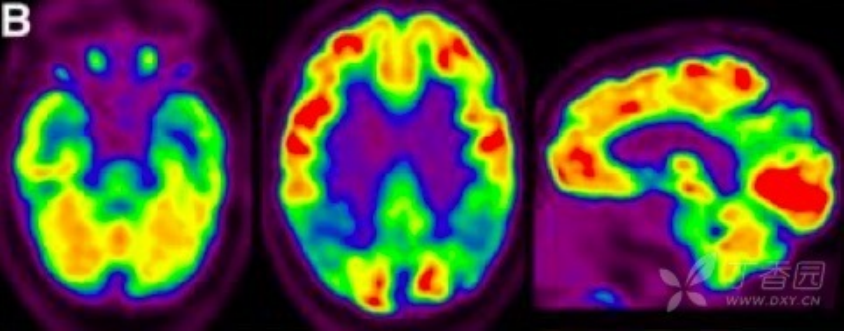

2.葡萄糖代谢 PET(FDG PET) FDG PET 用于测量神经元和胶质细胞的葡萄糖摄取情况,被认为是突触功能变化最敏感的指标。AD 患者可出现典型的颞顶区、后扣带回皮质和楔前叶葡萄糖代谢降低,具有 90% 敏感性以识别出 AD 与其他类型痴呆。也有研究发现,AD 早期颞叶出现高代谢,提示可能为疾病早期代偿表现。携带载脂蛋白 APOEε4 等位基因认知正常受试者也被发现与 AD 相似脑区的代谢异常。因此,作为衡量脑功能改变的指标,FDG PET 对 AD 疾病进展过程中脑功能改变的评估诊断价值更高。

3 AD 患者的 18F-FDG PET 成像